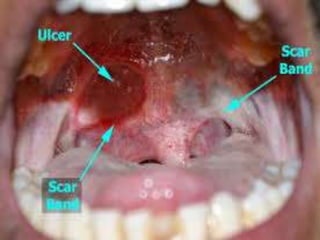

INDICATIONS:

Severe recurrent aphthous stomatitis,

Behcet's syndrome,

pemphigus vulgaris,

pemphigoid,

erythema multiforme



Recurrent aphthous stomatitis:

These superficial painful ulcers occur commonly in the

oral cavity.

Minor form of the disease has 1 to 5 ulcers at one

episode.

The ulcers which are under 1 cm in diameter persist 8 to

14 days, and heal spontaneously without sequelae.

major aphthous ulcers are larger than 1 cm, and persist

for weeks to months.

Corticosteroids either alone or in combination with other

drugs have been used for treatment of these lesions.

Topical steroids, such as triamcinolone acetonide and

prednisolone (2 times/day), are formulated as oral

pastes.

Therapeutic benefit can be derived from a mouthwash

containing betamethasone. It shouldbe noted that the

long-term use of topical steroids may predispose patient

to developing oral candidiasis.

Topical and injectable (intralesional) corticosteroids are

useful for large and painful lesions.

Systemic administration of corticosteroids is reserved for

severe cases to prevent lesion formation or to reduce the

number of lesions.

Systemic corticosteroids should be prescribed in short

courses, and only for severe outbreaks or cases that don't

respond to topical or injectable corticosteroids.

Behcet's syndrome:The treatment of oral lesions of

Behcet's syndrome is similar to the treatment of severe or

major RAS.